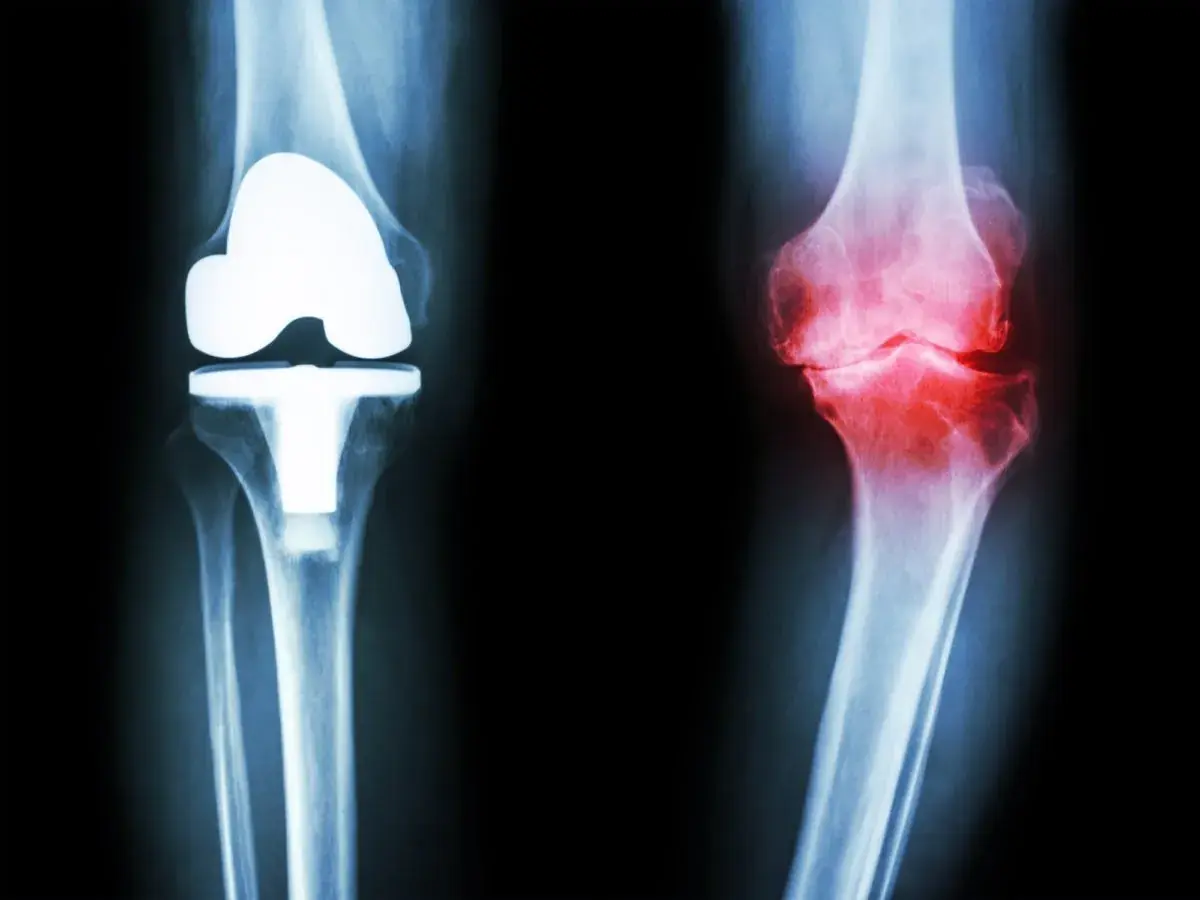

“Knee Pain Isn’t Always Normal—Here’s What to Watch